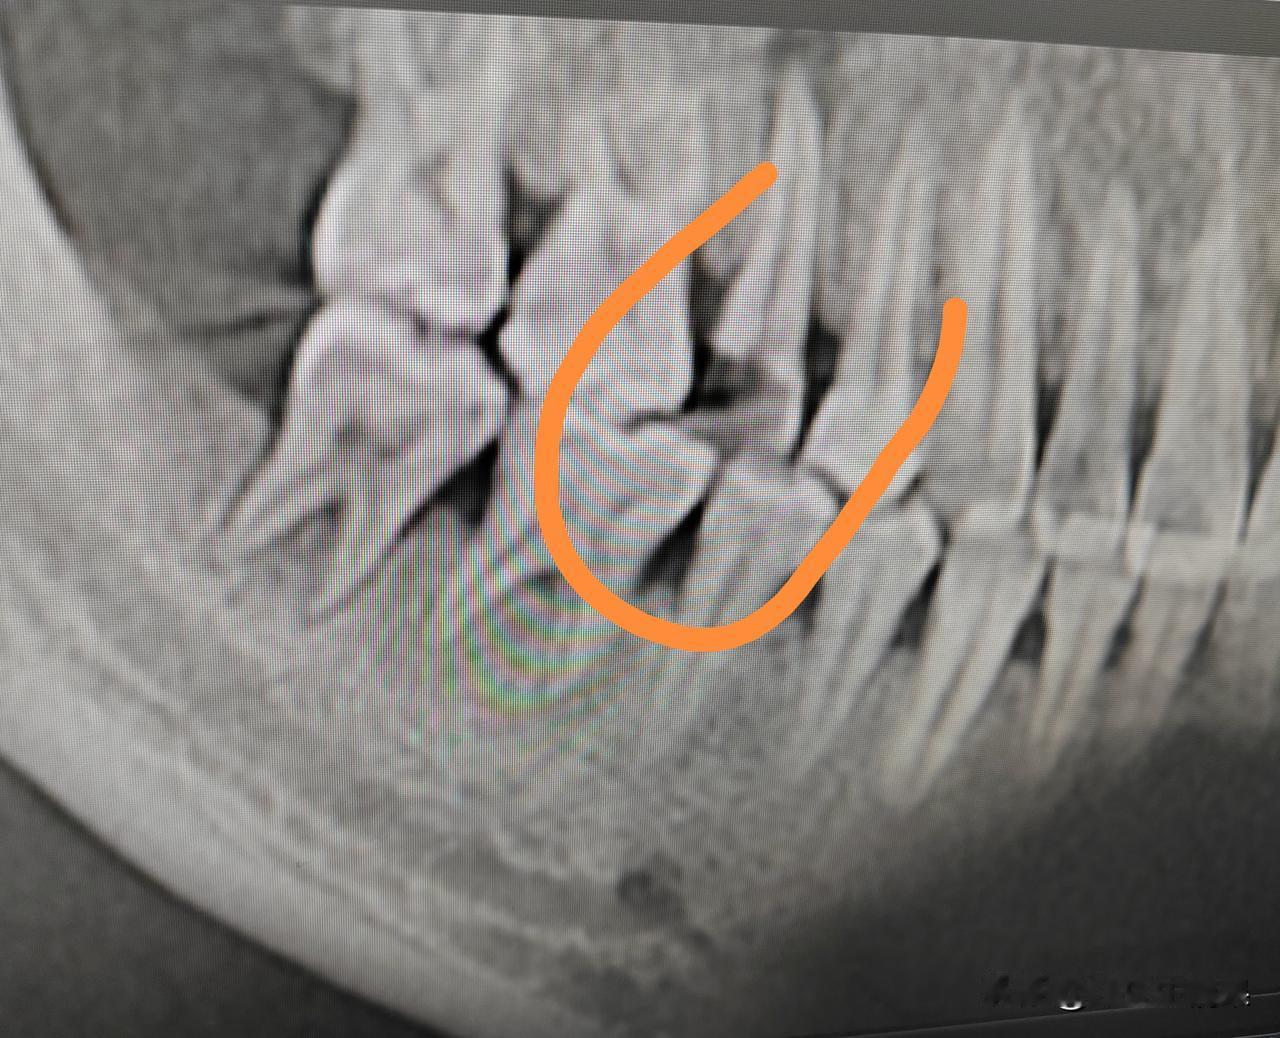

这颗牙齿蛀牙了,缺失的有点严重,CT显示根尖也有炎症,三甲医院的医生直接说拔掉或者根管治疗加打桩戴冠。 又说根管治疗加打桩戴冠和种牙价格差不多,我直接懵逼了,根管治疗网上不是说才一千多吗?种牙要一个W的价格,而且种牙不确定因素多。最后我还是选择做根管治疗,先保留自己的真牙。 真没有想到,三甲医院的医生,也这么坑,一般好医生不是优先让患者,选择保留真牙吗?